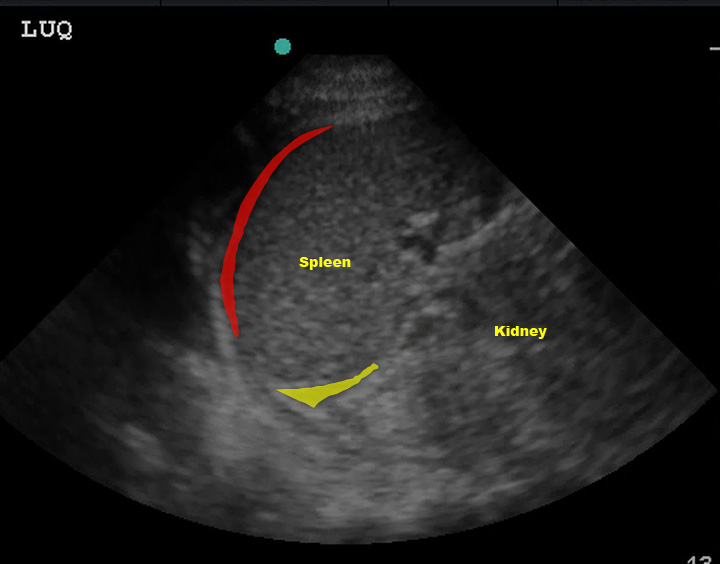

Just like the RUQ, fluid can appear in the splenorenal recess. HOWEVER, the trickiest part of evaluating the LUQ is that fluid is most likely to be found in the subphrenic space, between the spleen and diaphragm.

(Figure 31/31.1)

In the above picture, the red represents subphrenic fluid and the yellow denotes fluid in the splenorenal space.

(Figure 32/32.1)

In this picture above, note the large amount of fluid in the subphrenic space (yellow) despite the lack of fluid in the splenorenal space. Also note the fluid in the left thorax (red).